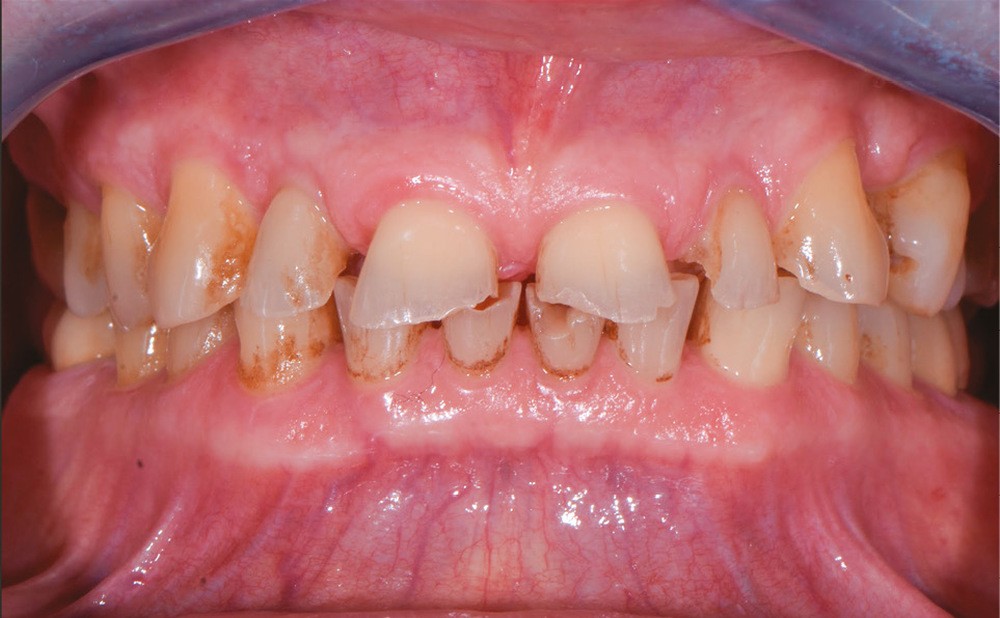

Un patient âgé de 69 ans se présente en consultation pour des problèmes d’ordre fonctionnel et un sourire dégradé. Selon l’adage de Peter Dawson, « l’esthétique et la fonction vont main dans la main », ce cas clinique illustre une situation instable et dysfonctionnelle qui ne sera résolue qu’avec une réhabilitation de la fonction et de l’esthétique (fig. 1 et 2).

Avant tout acte clinique, une étude approfondie est indispensable, nécessitant des données biologiques, occlusales, fonctionnelles et esthétiques. Un examen clinique approfondi et des examens complémentaires (radiologiques, électromyographiques, etc.) permettent de poser un diagnostic et d’envisager une planification thérapeutique (simulation, séquence, évaluation d’un pronostic).